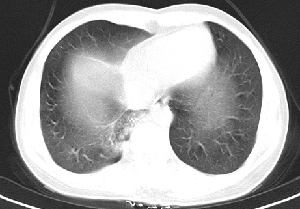

下叶后基底段近膈面见一椭圆形密度均匀增高的阴影,边界较清,其长轴指向内后方,考虑肺隔离症,建议增强扫描了解与主a联系!

右下肺隔离症可能性大,不除外炎性假瘤、神经原性肿瘤

1炎性假瘤,2神经原肿瘤待除外.

考虑:右下肺隔离症可能性大,不除外炎性假瘤,谨慎点+神经原性肿瘤,支持20楼

1.后纵隔神经原肿瘤,2.炎性假瘤。建议密切结合临床或抗炎治疗后复查。